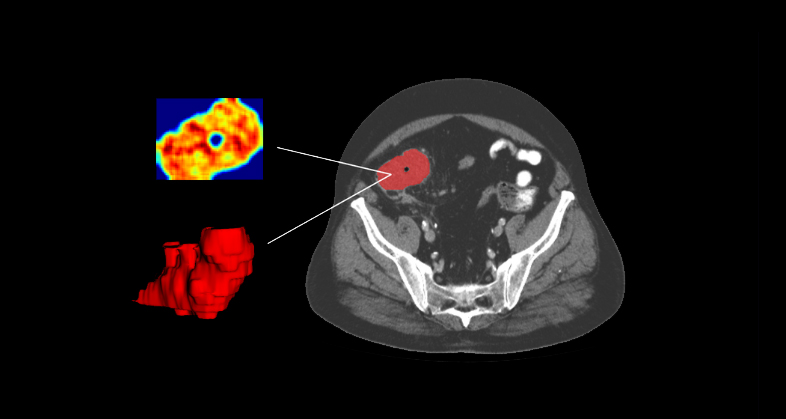

Whole body 18F-FDG PET/CT imaging exam of a patient with DLBCL in the coronal plane (left) and segmentation mask where every lesion is a unique label (right)

The standard therapy for diffuse large B-cell lymphoma (DLBCL) – R-CHOP – is ineffective in about one-third of patients. Early identification of these patients is crucial for testing alternate treatments. In a retrospective study, we explored the predictive value of 18F-FDG PET/CT imaging (radiomic and conventional PET parameters), clinical data, and genomic parameters, either alone or combined, for a complete response to first-line treatment in newly diagnosed DLBCL.

The combination of 18F-FDG PET/CT-derived imaging features (GLSZM_GrayLevelVariance, Sphericity, and GLCM_Correlation), clinical variables, and genomic data successfully predicted complete response to first-line treatment in DLBCL patients, with BCL6 amplification being the most predictive genetic marker. The combined model (radiomic plus clinical data) built using LDA and including genomic data showed an AUC of 0.904, 90% balanced accuracy vs AUC of 0.891, 80.7% balanced accuracy for the model that combined clinical data plus radiomic features.